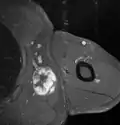

Medical imaging

Medical ultrasonography and magnetic resonance imaging (MRI) of liposarcomas are helpful and often essential in determining their extent, surgical accessibility, and relationship to any observed organ dysfunctions. Since ultrasonography is usually unable to distinguish a liposarcoma from a benign lipoma, MRI is the initial imaging of choice to provide evidence relative to making this distinction.[67]

In myxoid liposarcoma, it shows low signal intensity mass with high signal intensity foci on T1-weighted MRI images. The mass shows high signal intensity on T2-weighted images. This is because it contains predominantly mucoid substance (accounts for low signal intensity on T1) and small amount of mature fat (accounts for high signal intensity on T1).[68] The mass is well-defined, lobulated, multiloculated, or oval in shape without any infiltration into surrounding structures.[68]

Fig. 7 MRI of myxoid liposarcoma of high grade, in the left axillary region of 40-year-old man, highlighted by its white color, in this horizontal section of the tumor.